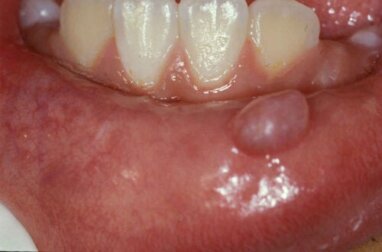

Mukozelen manifestieren sich unvermittelt als kleine, mit Schleim gefüllte Bläschen oder Knötchen im Mund, meist an der Unterlippe. Sie können durchscheinend blau sein oder den gleichen Farbton wie die darunter liegende Schleimhaut haben. Darüber hinaus sind sie nicht schmerzhaft, es sei denn, es liegt eine Wunde vor.

Obwohl viele Menschen sie mit einem Mundgeschwür verwechseln, handelt es sich bei diesen jedoch um geschwürartige Läsionen mit rötlichen Rändern und weißen Zentren. Außerdem verursachen Mundgeschwüre häufig Schmerzen und Unbehagen. Mukozelen treten besonders häufig an der Unterlippe auf. Allerdings können sie sich auch auf der Zunge, dem Gaumen, der Wangenschleimhaut und dem Mundboden bilden.